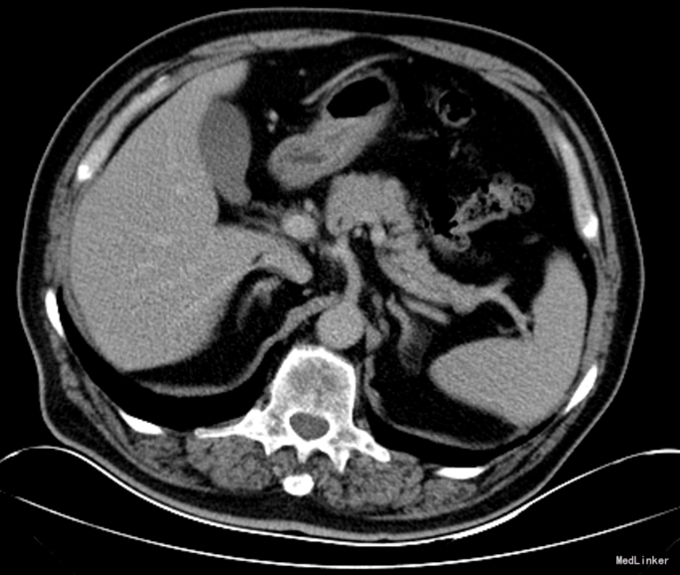

查体:体温36.5℃,呼吸:18次/分,心率89次/分,血压115/79mmHg。神清语明,步入病房,查体合作。贫血貌,周身皮肤及粘膜无黄染及出血点,浅表淋巴结未触及肿大,颈静脉无充盈。巩膜无黄染,睑结膜苍白,口唇无发绀。双肺听诊呼吸音清,双肺未闻及明显干湿罗音。心音低钝,律齐,听诊心率66次/分,各瓣膜听诊区未闻及病理性杂音。腹部无压痛,无反跳痛及肌紧张,肝脾肋下未触及,无肝肾区叩击痛。双下肢无水肿。 辅助检查:腹部增强CT:胃窦部小弯侧溃疡病变,恶性可能性大。

诊断:胃癌;中度贫血;冠心病陈旧性心肌梗死;高血压2级(极高危);冠脉造影及支架植入术后 治疗:全麻下行胃癌根治切除(D2)、Billorth-I式吻合、空肠营养造瘘术,手术顺利,术后恢复可,术后第7天,患者突然出现右侧腹部疼痛,后转移至下腹及左侧髂腹部等,吻合口后引流管引流出暗黄色浑浊液体,留置胃管后引流出同性质液体,考虑吻合口瘘,复查全腹CT平扫,肝周积液较前增多。请介入科行肝周积液的穿刺引流,同时经空肠营养管予肠内营养,但患者仍持续高热,经介入科第二次穿刺引流后,患者体温由39.5℃逐渐下降至正常。